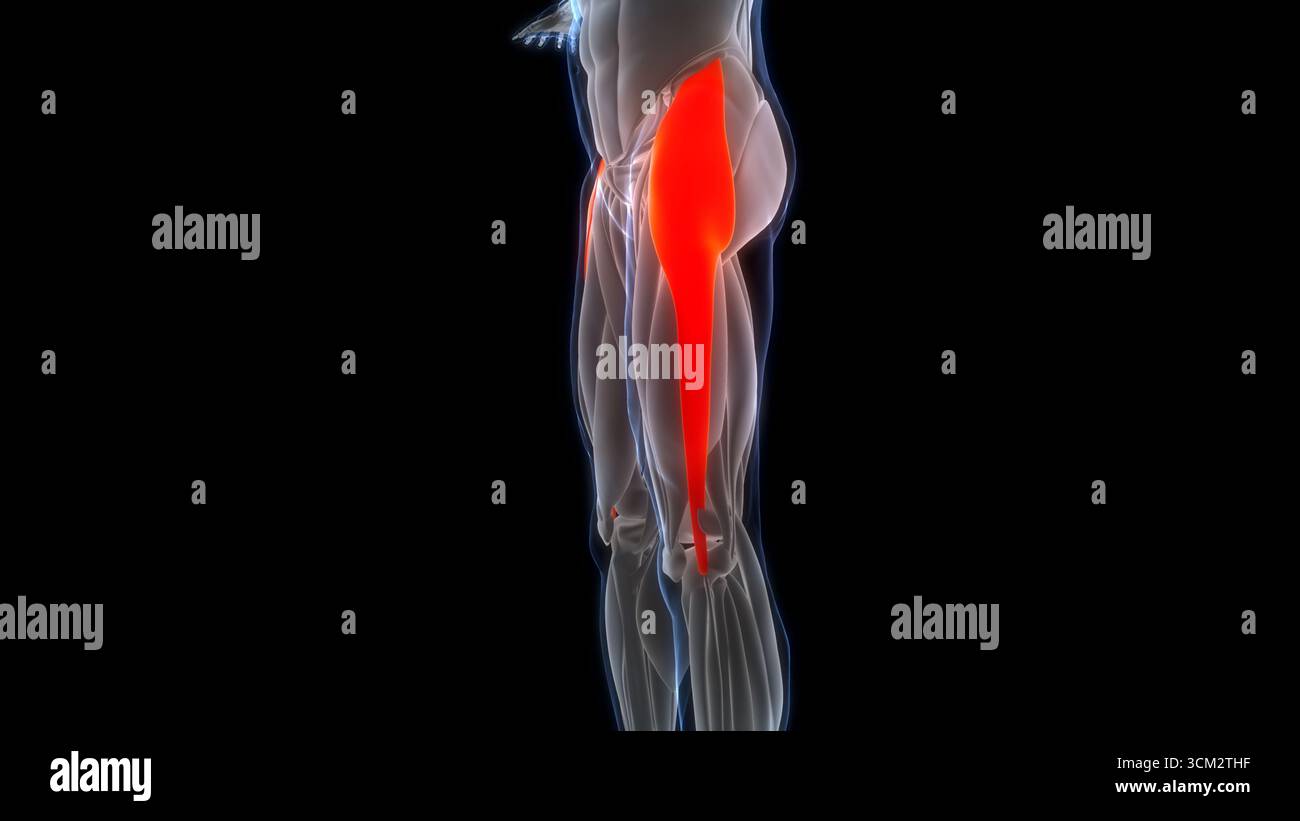

Human Muscular System Leg Muscles Tensor Fasciae Latae Muscles Anatomy Stock Photohttps://www.alamy.com/image-license-details/?v=1https://www.alamy.com/human-muscular-system-leg-muscles-tensor-fasciae-latae-muscles-anatomy-image700771049.html

Human Muscular System Leg Muscles Tensor Fasciae Latae Muscles Anatomy Stock Photohttps://www.alamy.com/image-license-details/?v=1https://www.alamy.com/human-muscular-system-leg-muscles-tensor-fasciae-latae-muscles-anatomy-image700771049.htmlRF3CM2THD–Human Muscular System Leg Muscles Tensor Fasciae Latae Muscles Anatomy